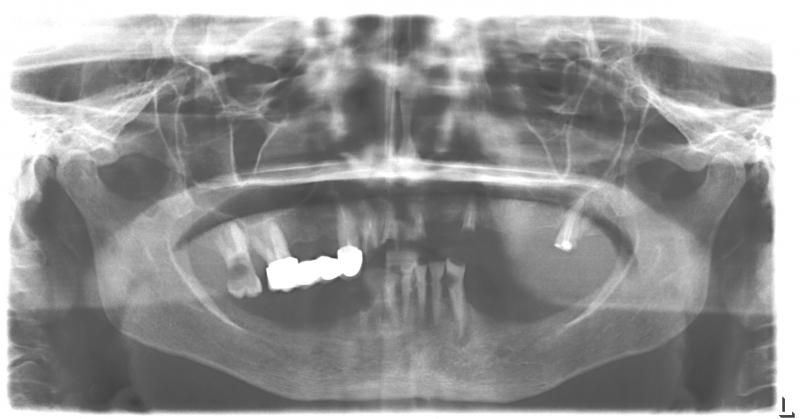

Установка 10 имплантантов на беззубую челюсть с помощью компьютерной программы: Через 2 недели после операции

Через 2 недели после операции